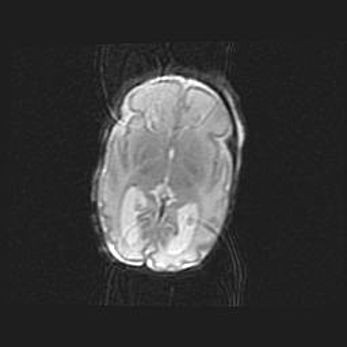

Сообщающаяся гидроцефалия. Кистозная энцефаломаляция головного мозга.

Возраст: 3 месяца 4 дня

Вес: 3100 г

Пол: женский

Окружность головы: 34 см

Срок гестации: 31 неделя

Кистозная энцефаломаляция головного мозга - одна из форм поражения головного мозга в детском возрасте. Характеризуется возникновением множественных и распространённых кист в коре, белом веществе и подкорковых образованиях головного мозга у плодов, новорождённых и детей раннего возраста. Развитие кистозной энцефаломаляции связано с внутриутробной асфиксией и гипотонией, родовой травмой, тромбозом синусов, пороками развития сосудов, инфекциями, сепсисом и другими причинами. Наиболее значимые инфекционные агенты: вирусы простого герпеса, цитомегалии, краснухи, токсоплазмы, энтеробактерии, золотистый стафилококк и другие.